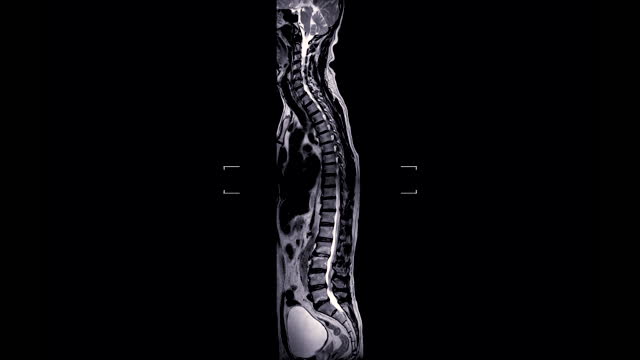

척추관협착증은 척추 주변의 근육과 인대가 퇴행하여 척추관 내 황색 인대가 비정상적으로 부풀어 오르면서 발생하는 퇴행성 척추질환 중 하나입니다. 이 질환은 가까운 거리도 통증으로 인해 걷기가 어려워지는 특징을 가지고 있으며, 새벽에 다리에 통증을 느끼는 경우가 많습니다.